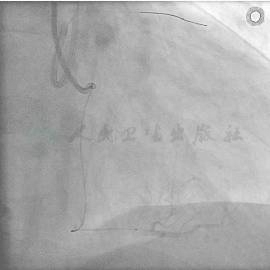

冠状动脉造影结果

经右侧桡动脉径路,6F血管鞘,造影结果发现:LM正常(图1);LAD在S1发出处完全闭塞,看不到断端(图2);LCX正常,向LAD形成侧支循环1级,心外膜途径,极度迂曲,直径较大(图3)。RCA正常,向LAD形成侧支循环1级,间隔支途径,迂曲较少,直径偏小(图4)。

图2 LAD在S1发出处完全闭塞,看不到断端